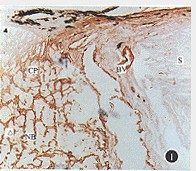

常成人视乳头Ⅳ型胶原蛋白免疫过氧化酶染色

常成人视乳头Ⅳ型胶原蛋白免疫过氧化酶染色,▲筛板前区,CP筛板,△筛板后区,S巩膜,BV血管,NB神经膜 纵切观察 ×6